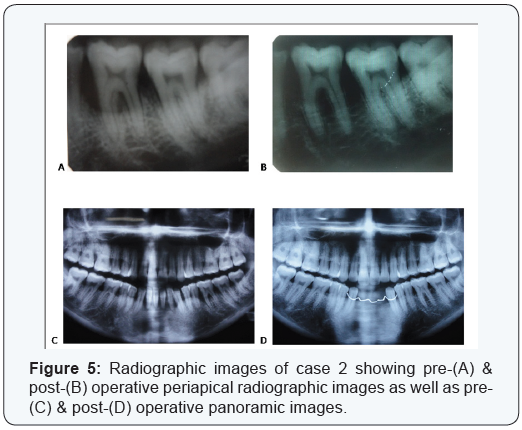

Two cases are presented in figures from 2 to 5 with clinical photographs during surgical intervention and pre-& postoperative radiographic images. Case 1 is presented in figures ( 1 & 3) and was treated by using bio absorbable equine collagen membrane, for covering and treatment of selected intrabony defect site between teeth No. 26 & 27 as mainly distal to tooth No. 26. Case 2 is presented in ( figures 4 & 5 ) and was treated by the application of the same bio absorbable collagen membrane but in combination with equine bone as xenograft material, for covering and treatment of selected intrabony defect site between teeth No. 35 & 36 as mainly mesial to tooth No. 36.

Standardized intra-oral periapical radiographs (Kodak X-ray film, USA) were obtained at baseline and 18 months postoperatively. These radiographs were taken using long cone/ extension cone paralleling technique with a positioning device mounted on a roentgen machine, operating at 70 Kilo Voltage Power.

Radiographs were scanned using a digital scanner at an input of 300 dpi and 100% scale, then they were analyzed using a software@. The images had 768 × 512 pixels and 256 gray scale level. The alignment of images, in the pairs of radiographs, was applied to correct small geometric misalignments. Gray level was then calibrated to indicate changes in the radiographic density (RD).

In addition, the following measurements were obtained in millimeters: distance from cementoenamel junction (CEJ) to base of the defect (BD) and from CEJ to alveolar crest (AC). The differences between baseline and 18-month postoperative values for CEJ–BD indicated the change in the radiographic defect depth (RDD), whereas the differences for CEJ–AC suggested the possible occurrence of crestal bone resorption (CBR).